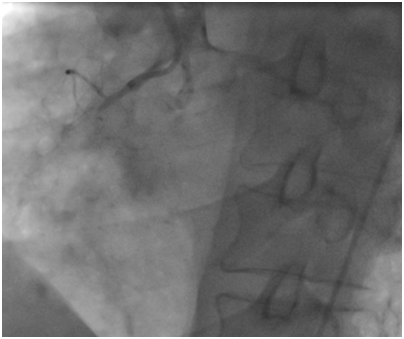

The first case

A 53year-old male without cardiovascular risk factor was admitted to our hospital in 2005 due to an inferior AMI. The culprit lesion was thrombotic occlusion of proximal right coronary artery (RCA). Primary percutaneous coronary intervention to RCA with a BMS (3.00x24mm; Liberté®; Boston scientific, Natick, Massachusetts) was done with an excellent result. No post-dilatation was needed. Dual antiplatet therapy was prescribed for one month (Clopidogrel 75mg once a day). Then; aspirin (ASA) was prescript alone for life. Eight years later, he suffered from a severe chest pain relevant to a recurrent inferior AMI. Hence, he was immediately referred for a primary angioplasty. In-stent huge thrombosis was located in the proximal edge of the stent of the RCA. IC stent® (Siemens Healthcare GmbHErlangen, Germany) had showed an underdeployment of the stent. Then, a predilatation with a non compliant Balloon had restored a TIMI III flow. He was discharged five days later with a daily 75mg of clopidogrel for 12months and 100mg of ASA associated daily for life (Figure 1-3).

Figure 1 Thrombotic occlusion at the proximal edge of the bare metal stent.